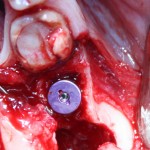

С помощью аналога импланта, входящего в хирургический набор Friadent Xive, можно проверить правильность подготовки лунки и позиционирование будущего импланта:

Аналог импланта должен прочно удерживаться стенками лунки, не обладать излишней подвижностью и не проваливаться.

В данном случае, я использую Friadent Xive диаметром 4,5 мм и длиной 13 мм. Как видно по рисунке 7, сам имплантат несколько больше корня удаленного зуба но, в целом, соответствует ему. Разница в размере позволяет обеспечить качественную первичную стабилизацию импланта.

Имплантат устанавливается в подготовленную лунку:

Имплантат позиционируется более язычно и прилегает к внутренней стенке альвеолы. Такое положение наиболее оптимально с точки зрения распределения жевательной нагрузки и эстетического результата.

Обратите внимание, что имплантат не погружается слишком глубоко. Его шейка находится на одном уровне с шейками естественных зубов. Чрезмерное заглубление импланта может привести к потере костной ткани и рецессии десны в области соседних зубов.